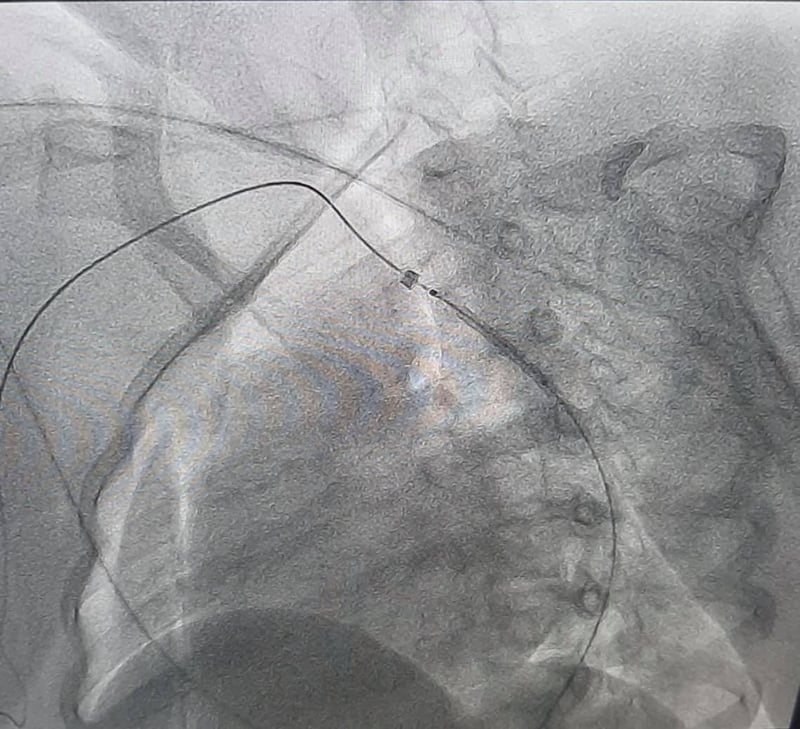

Під час обстеження у дівчинки виявили вроджену ваду серця – коарктацію аорти. Це стан, при якому наявне звуження просвіту аорти, внаслідок чого розвивається підвищений тиск у верхній половині тіла.

За допомогою сучасних технологій на основі результатів обстеження була проведена віртуальна реконструкція анатомії аорти та її гілок, що допомогло медикам обрати найбільш сучасну та малотравматичну тактику подальшого лікування.

Вроджену ваду судини було ліквідовано за допомогою спеціальної процедури – встановлення стенту у просвіт судини. Результат лікування не забарився й одразу після оперативного втручання у дитини нормалізувався артеріальний тиск, а також зникла різниця тиску між верхніми та нижніми кінцівками.